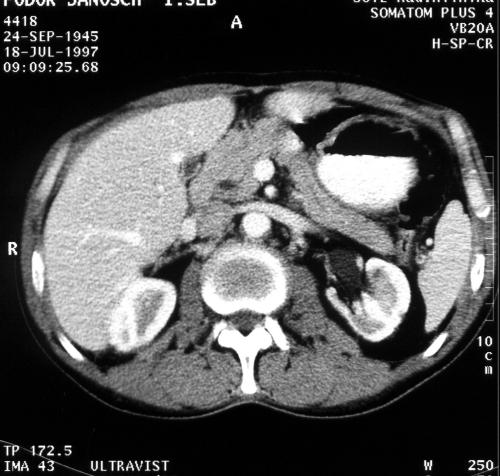

Figure 1. A 56 year old male with epigastric pain and loss of weight. CT after contrast medium administration shows a non-homogeneous hypodense nodule in the dorsal part head of the pancreas. Ductal adenocarcinoma

A circumscribed mass is the primary, but not necessarily an early sign of ductal pancreatic adenocarcinoma. An increase in diameter and roughness of the contour of the pancreas are unreliable signs of malignancy. The masses contained a central zone of diminished attenuation in about 80% of the cases [4]. On unenhanced CT most tumors have the same density as normal pancreatic tissue and can easily be missed if the tumor is small and the contour of the gland is not deformed. With spiral CT and bolus contrast administration, the tumor-pancreas contrast is best seen during the early phase of pancreatic perfusion. The tumor as a hypodense lesion can be distinguished from the opacified pancreatic parenchyma. A cystic central portion can demonstrate necrosis or the hemorrhage in the tumor. The border between the pancreas and the retroperitoneal space and the surrounding organs is often indistinct [5].

The pancreatic duct and/or common bile dilatation is critically indicative of malignancy. After intravenous contrast enhancement, dilatation of the biliary tract becomes clearly visible and the contour of the pancreatic duct can be better evaluated [6, 7].